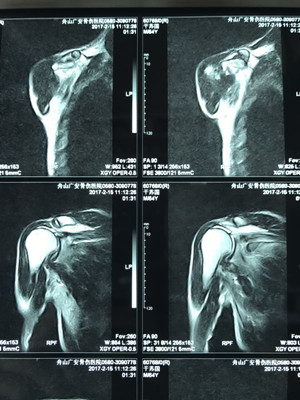

據(jù)了解,干大伯半年前因外傷導(dǎo)致頸椎外傷伴截癱,右肩關(guān)節(jié)脫位伴巨大肩袖斷裂,曾在廣安醫(yī)院接受頸椎手術(shù),術(shù)后恢復(fù)良好。后來,干大伯要求進(jìn)一步對肩關(guān)節(jié)進(jìn)行治療。廣安醫(yī)院副院長危立軍及運動醫(yī)學(xué)科主任羅軍對其進(jìn)行詳細(xì)檢查后,認(rèn)為干大伯的右肩存在巨大不可修復(fù)肩袖撕裂伴嚴(yán)重的關(guān)節(jié)炎,肩袖的脂肪浸潤達(dá)到四級,治療上有一定的挑戰(zhàn)性,只能通過特殊類型的人工肩關(guān)節(jié)——反式全肩人工關(guān)節(jié)來重建關(guān)節(jié)功能。